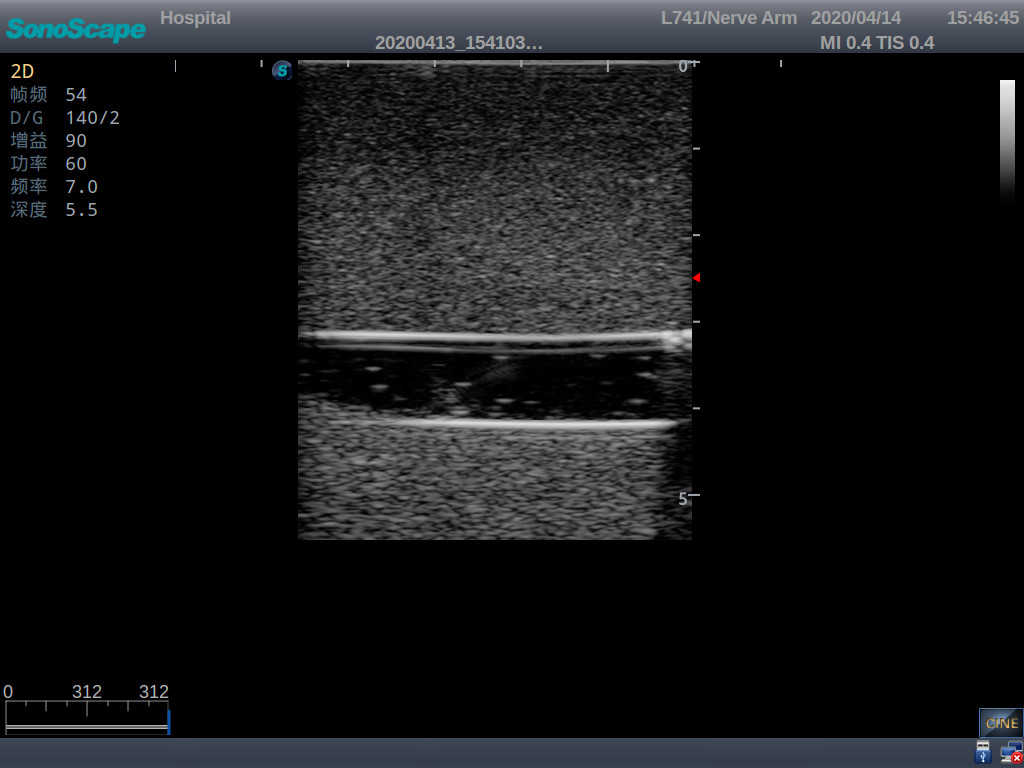

2)   It can be used by real ultrasound machines

3)   Clear and real images of the tissues and organs (basilic vein and superior vena cava)

5)   Observe the guide wire marches